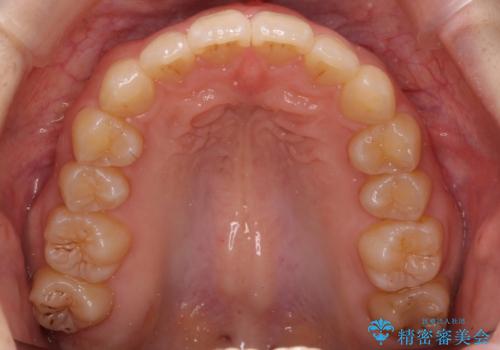

奥歯のかみ合わせも妥協しない インビザライン治療

インビザライン治療は主に奥歯のかみ合わせが大きな問題がない場合は特に問題なく終了しますが、今回のケースのように奥歯のかみ合わせが悪い場合、しっかり治らないことがあります。

患者様が気づかない範囲で妥協して終わるということをせず、しっかり奥歯に部分矯正を用いて大きな問題を解決してからインビザライン治療に入りました。

下の前歯を一本抜歯しています。(抜歯の本数は最小限にしています。)